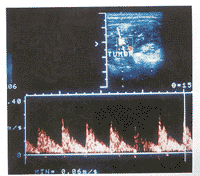

图3 血管瘤内动脉血流多普勒频谱,收缩期最高流速为118 cm/s,舒张期最低流速为53 cm/s,RI=0.55

血管瘤在高频灰阶超声图像上均表现为一中等偏低回声的实质性团块(图1),呈类圆形或不规则形,边界清楚,内呈网格状。1例患者(4.5%)病变内可见散在钙化灶。多普勒超声见肿块内血流信号丰富,血管密度为3~8条/cm2[(5.3±2.0)条/cm2],PSV为23~118 cm/s[(61.1±29.9)cm/s],RI为0.5~0.8(0.6±0.1)(图2,3)。